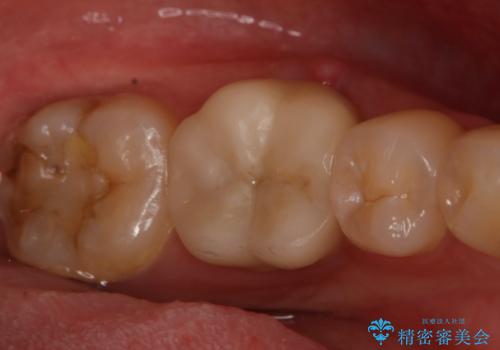

左下奥歯が腫れて痛い フルジルコニアクラウン

- 左下大臼歯の歯肉に腫れと痛みが繰り返し起こっているので治療を希望し来院された患者様です。

既に治療されている歯でしたが根尖部に病巣が確認出来たので、精密根管治療とクラウンの再治療が必要と判断されました。

精密根管治療を行なったことで病巣は消失し、腫れや痛みは再発することなく経過は良好です。

被せ物はフルジルコニアクラウンを選択されました。